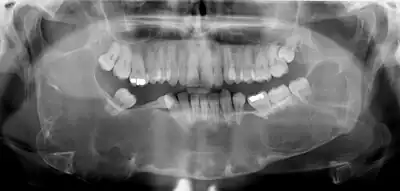

Large odontogenic keratocyst with impacted wisdom teeth superficial to lesion